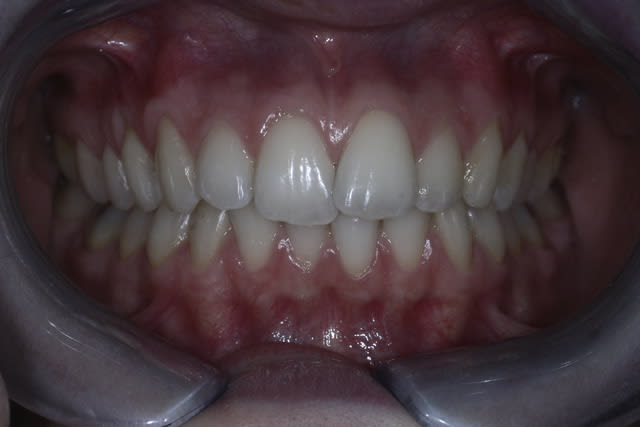

Cett jeune patiente refuse l'ODF "classique" mais veut faire qqchose pour corriger le chevauchement.

Cette "jeune" patiente.... jeune oui mais quel âge exactement?

Sinon, elle fonctionne comment? Déglutition, respiration, habitudes de mastication (à droite, à gauche, des deux côtés?)...

Elle serre, elle bruxe, elle se ronge les ongles, elle ronfle???

Oui une gouttiere invisalign ou invisalign like pourrait aider mais je doute que ce soit stable, de même un plaque palatine avec verrin d'expension (peut être) et un petit resssort derriere la centrale pourraient marcher mais perso ce serait soulet et besombes conformateur n°5 ou expansion n°3 et on attend quelques mois histoire de voir. Le sb pourrait sans doute lever sa supra par la même occsaion et expanser les arcades.

j'ai l'impression qu'elle a une occlusion quasi idéale sur la photo.

vu l'usure de ses dents et ses bords libres, je dirais qu'elle bruxe pas et qu'elle se ronge pas les ongles non plus.

C'est séduisant (et pas cher), j'ai aussi l'impression que les arcades sont étroites et manque d'expansion (respiration buccale ?), cependant on note déjà quelques récessions gingivale aux collets des 23, 14...N'y a t-il pas un risque d'accentuer cet état lors de l'expansion.

Le SB permet-il aussi un réglage assez fin pour réaligner les collet de 11 et 21 (il y a 1 bon mm de décalage pour l'instant)?